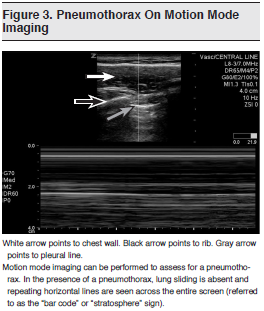

The traditional FAST examination involves 4-quadrant scanning with views of the hepatorenal space, the perisplenic and splenorenal interface, the pelvis, and the pericardium through a subxiphoid or parasternal approach. Recently, authors have studied an extended version of the FAST examination, referred to as the Extended Focused Assessment with Sonography for Trauma (E-FAST). In addition to the 4-quadrant views of the FAST, the E-FAST includes views of both hemithoraces at the levels of the diaphragm-abdominal interface and over bilateral anterior chest walls. (See Figure 3) It is designed to assess for pneumothorax in the anterior views and for pleural effusion or hemothorax in the supradiaphragmatic views.

Evaluation of the patient with thoracic trauma begins with an examination for external injuries and auscultation of lung sounds, usually followed by radiographic evaluation with a portable supine anteroposterior chest x-ray. Unfortunately, the physical examination is frequently insufficient and carried out in a loud environment where diminished breath sounds are not easily appreciated. In addition, portable chest radiographs are not sensitive enough to rule out lung injury and have been estimated to miss traumatic pneumothoraces up to 50% of the time.16-21

The use of ultrasound to detect pneumothorax has been well established. Lichtenstein and Menu showed that in patients in the intensive care unit (ICU), bedside ultrasound has a sensitivity of 95.3%, a specificity of 91.1%, and a negative predictive value of 100% when compared with CT scanning as the reference standard for the detection of pneumothorax.22 In ICU patients with radio-occult pneumothoraces, the same group showed that ultrasound was superior to plain radiography for the detection of pneumothorax, with a specificity approaching 100%.23 Both of these studies were conducted in ICU patients in whom disease processes such as fibrotic lung disease and acute respiratory distress syndrome may affect the quality of the sonogram, resulting in both false-positive and false-negative studies.

In a prospective study of blunt trauma patients, Blaivas et al found that the sensitivity of ultrasound in detecting pneumothorax was 98.1% and the specificity was 99.2%, while chest radiography had a sensitivity of 75.5% and a specificity of 100%.16 An article by Rowan et al also compared the accuracy of sonography with supine chest radiography for the detection of traumatic pneumothorax. In 27 patients who sustained blunt thoracic injury, the radiographic and ultrasound findings were compared with CT scan results as the gold standard for diagnosis. Eleven of the 27 patients had pneumothoraces on CT and all 11 cases were detected with sonography. There was, however, 1 false-positive with ultrasound, resulting in a sensitivity of 100% and a specificity of 94%. Supine chest radiography had a specificity of 100% but a sensitivity of only 36%.17

Two studies by Soldati and colleagues also found highly superior sensitivity and comparable specificity for ultrasound when compared with chest x-ray, again using CT as the gold standard.18,19 In a prospective study of patients with blunt trauma, Zhang et al found a sensitivity of 86% and a specificity of 97% with sonography, while plain film had a sensitivity of 27.6% and a specificity of 100%. Of note, they found that the mean time needed to diagnose pneumothorax was significantly shorter with ultrasound than with chest x-ray (2.3 ± 2.9 vs 19.9 ± 10.3 min, P < 0.001).20 Kirkpatrick et al compared the value of supine chest radiography versus a handheld ultrasound device in 208 patients with blunt or penetrating trauma to detect pneumothorax during their initial resuscitation. The methods in this study differed slightly from those in previous studies in that they used both a composite standard (which included CT, chest x-ray, and the escape of air with tube thoracostomy) and CT as the gold standard in the comparison with the sonograms and chest radiographs. Ultrasound had a sensitivity of 58.9% and a specificity of 99.1% when compared with the composite standard and a sensitivity of 48.8% and a specificity of 98.7% when compared with CT alone; chest x-ray had a sensitivity of 20.9% and a specificity of 99.6% when compared with CT alone.21 Again, these results demonstrate the superiority of ultrasound over supine chest radiography for the detection of pneumothorax, although the sensitivity reported in this study is much lower than that described previously. As a possible explanation for the decreased sensitivity, the authors cite the technical limitations related to using a hand-held ultrasound device for trauma resuscitations.